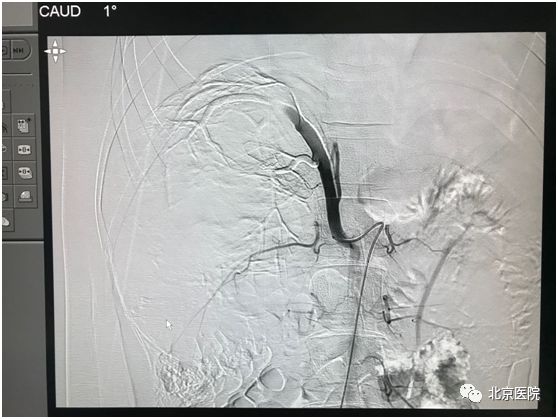

北京医院肿瘤微创治疗中心李晓光团队借助DSA影像技术,经股动脉局麻穿刺置管,利用介入手段对患侧肾动脉选择性造影,证实肿瘤供血动脉、肿瘤生长部位、大小、有无动静脉瘘,再利用超选技术确定目标血管行肾动脉栓塞术。次日该患者如期行“右肾癌根治术”。手术顺利,术中出血量少量,达到预期效果。

栓塞后可见肿瘤供血主干呈枯树枝样

1970年,Wholey首次将肾动脉栓塞术应用于临床,以控制肾癌术中出血。这一技术具有以下优点:1、减少术中出血,提高手术切除率。2、促进机体肿瘤免疫调控过程,选择性肾动脉栓塞后24~48h,自然*伤杀**(NK)细胞活性明显增强。3、姑息性治疗晚期肾癌,因肿瘤及瘤栓明显缩小,甚至瘤体坏死,增加手术切除的几率。4、提高了患者的生活质量,延长生存期。